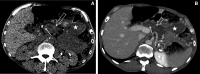

Splenic artery pseudoaneurysm (SAP) is a rare and dangerous diagnosis with a high risk of rupture and death. It is the most common cause of main pancreatic duct haematoma-haematosuccus pancreaticus (HP). Neither SAP nor HP have specific clinical features that allow diagnosis without cross-sectional imaging. Upper gastrointestinal haemorrhage and a history of pancreatitis should raise clinical suspicion but ultimately endoscopy and CT are required. We report a case of a 51-year-old man without clinical symptoms in whom cross-sectional imaging was undertaken for incidental severe acute anaemia. This demonstrated stigmata of chronic pancreatitis and the main pancreatic duct was distended with dense material in keeping with haematoma. The diagnosis of a SAP bleeding into the main pancreatic duct was made radiologically. A subsequent oesophago-gastro-duodenoscopy confirmed the diagnosis. The imaging appearances, pathophysiology and management are discussed.